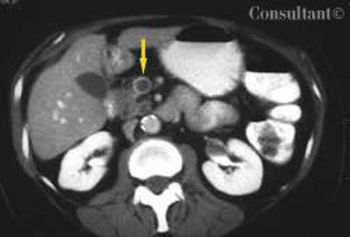

A 65-year-old woman with metastatic adenocarcinoma of the colon was undergoing chemotherapy following a colectomy and a hepatic wedge resection. The physical examination and laboratory data were unremarkable.